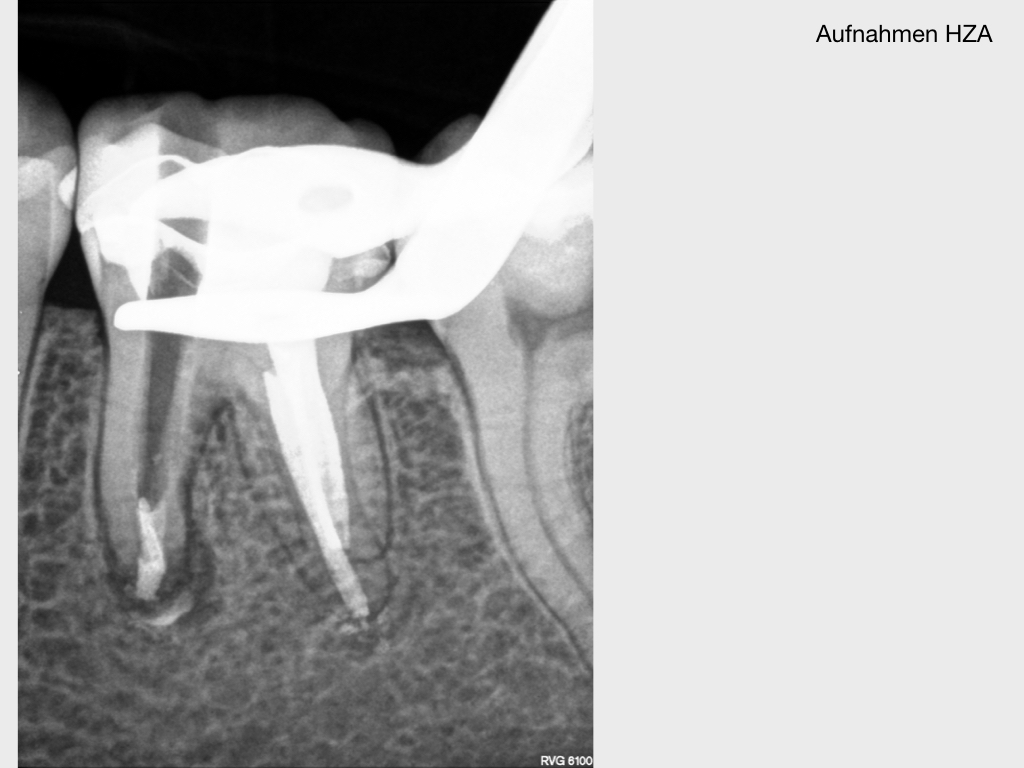

WSR2.007 Veröffentlicht 2. März 2020 am 1024 × 768 in Kurz berichtet – Z.n. WSR – Revision mit minimalinvasivem Zugang